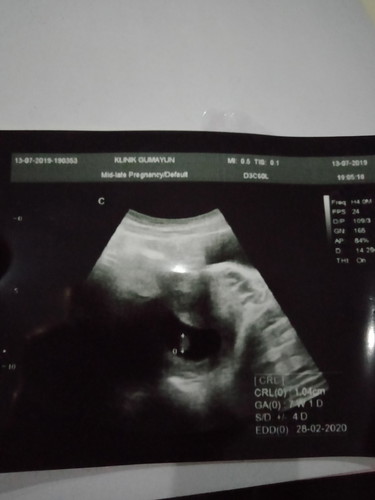

Bin maf say mau nanya ,setiap kali Usg hPl say sllu mundur , prtma usg 19 feb , usg kedua 21 feb , nah usg ketiga ini 28 feb... Itu normal gk ya bund .. dan u tk gmbrn Usg yg 7w adakh ygsma kygmbrn UsG saya ini?